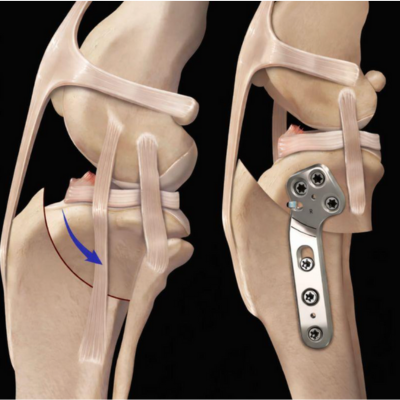

Concrètement, le chirurgien réalise une ostéotomie circulaire du tibia proximal, puis fait pivoter le plateau tibial afin de réduire son angle. Cette modification neutralise la « poussée tibiale craniale » qui, lors de l’appui, provoquait le glissement anormal du tibia sous le fémur. L’os est ensuite stabilisé à l’aide d’une plaque spécifique et de vis, généralement laissées en place à vie si elles ne provoquent aucune gêne.